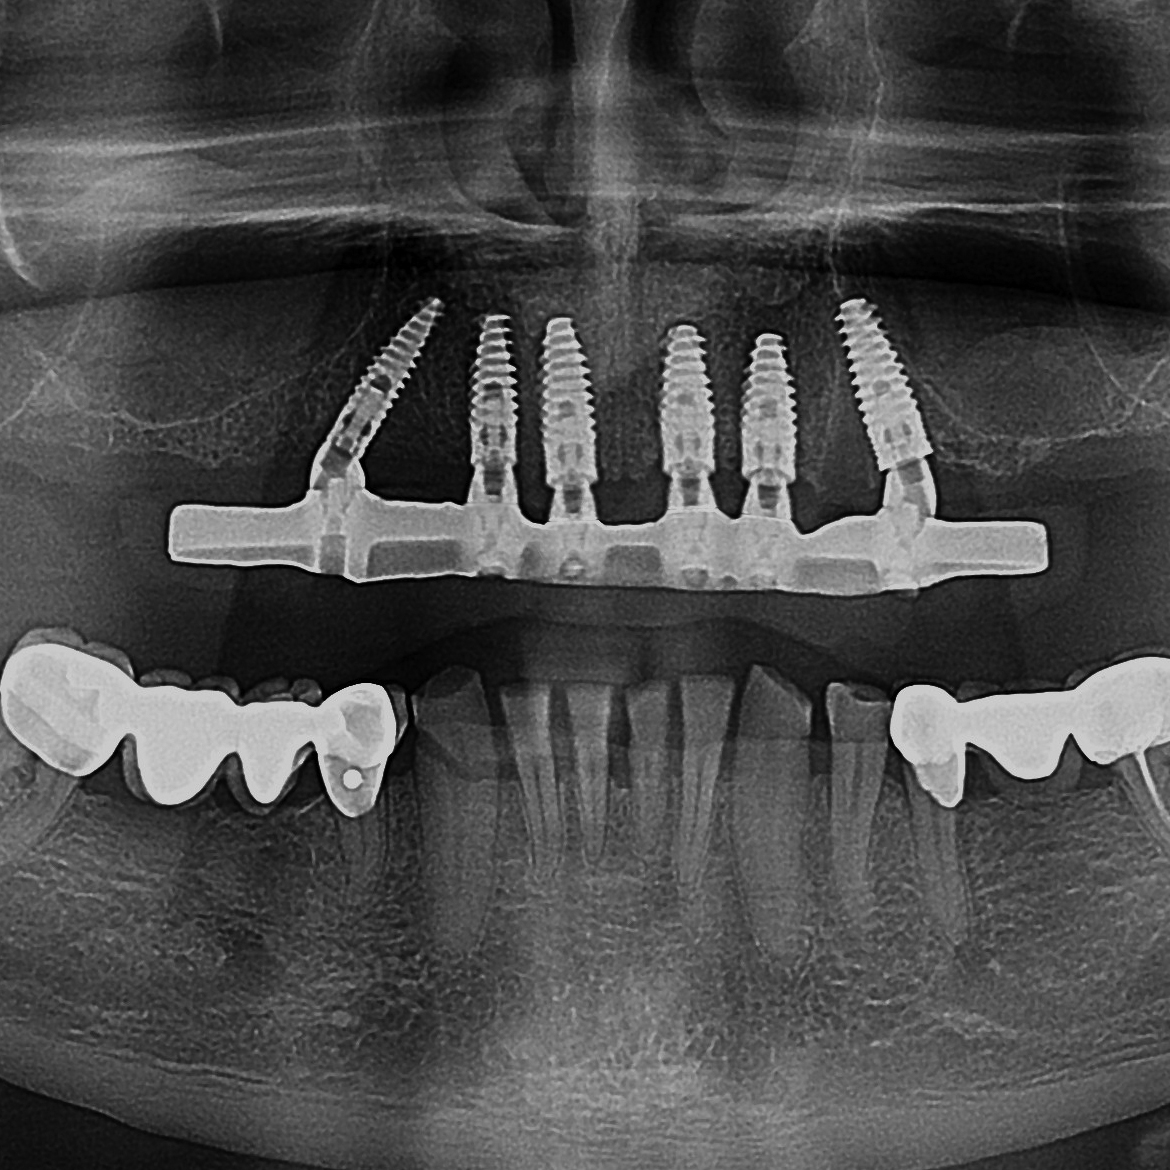

Öz Dental, Aydın’da diş hekimlerine yönelik dijital teknoloji destekli laboratuvar hizmetleri sunar. Tüm üretim sürecimiz; vaka odaklı planlama, CAD/CAM tabanlı hassas üretim ve çok aşamalı kalite kontrol anlayışıyla yürütülür. Amacımız, klinik beklentilere tam uyumlu, estetik ve uzun ömürlü restorasyonlar üretmektir.